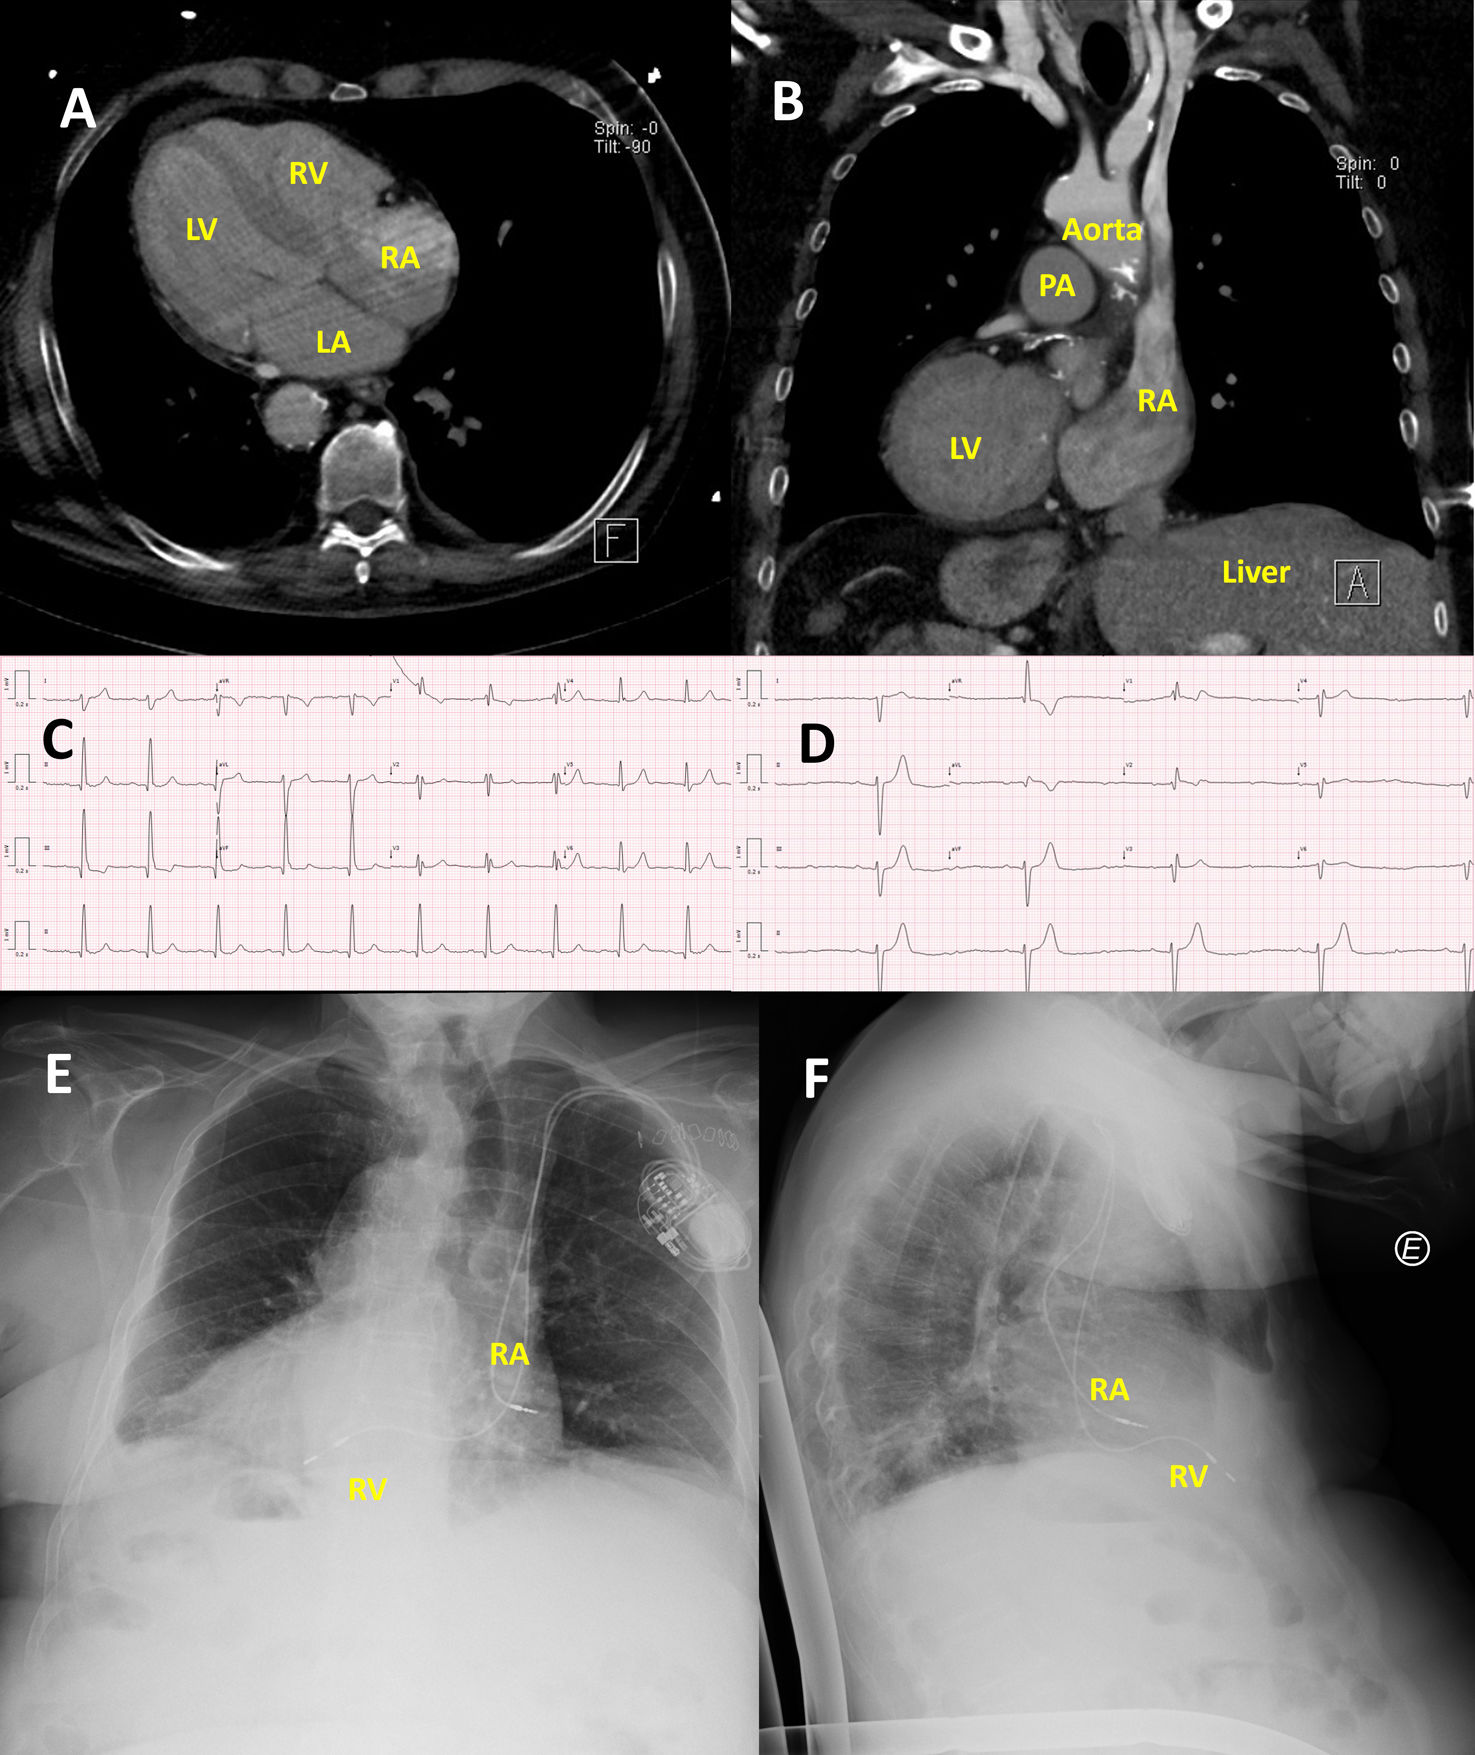

Dual-chamber pacemaker implantation in a patient with situs inversus totalis with dextrocardia. (A) Axial view and (B) coronal view of thoracic computed tomography scan showing mirror-image anatomy with dextrocardia, normal atrioventricular and ventriculoarterial connections, and right-sided liver. (C) Baseline ECG showing sinus rhythm with right bundle branch block and left posterior fascicular block. (D) ECG performed after syncope revealing trifascicular block with second-degree atrioventricular block Mobitz type II. (E) Posteroanterior and (F) lateral chest radiographs demonstrating left-sided pacemaker generator with transvenous leads directed toward the right atrial appendage and right ventricular apex, confirming successful pacemaker implantation. LA: left atrium; LV: left ventricle; RA: right atrium; RV: right ventricle; PA: pulmonary artery.

The chest X-ray showed situs inversus, leading to a thoracic computed tomography scan to confirm the venous anatomy. The computed tomography scan confirmed the complete mirror-image anatomy and excluded venous drainage abnormalities (Figure 1A and B). Despite the unusual anatomy, a dual-chamber pacemaker was successfully implanted in the left prepectoral region via ultrasound-guided axillary vein puncture. Atrial and ventricular leads were positioned in the right atrial appendage and right ventricular apex, respectively (Figure 1E and F), with appropriate electrical parameters.